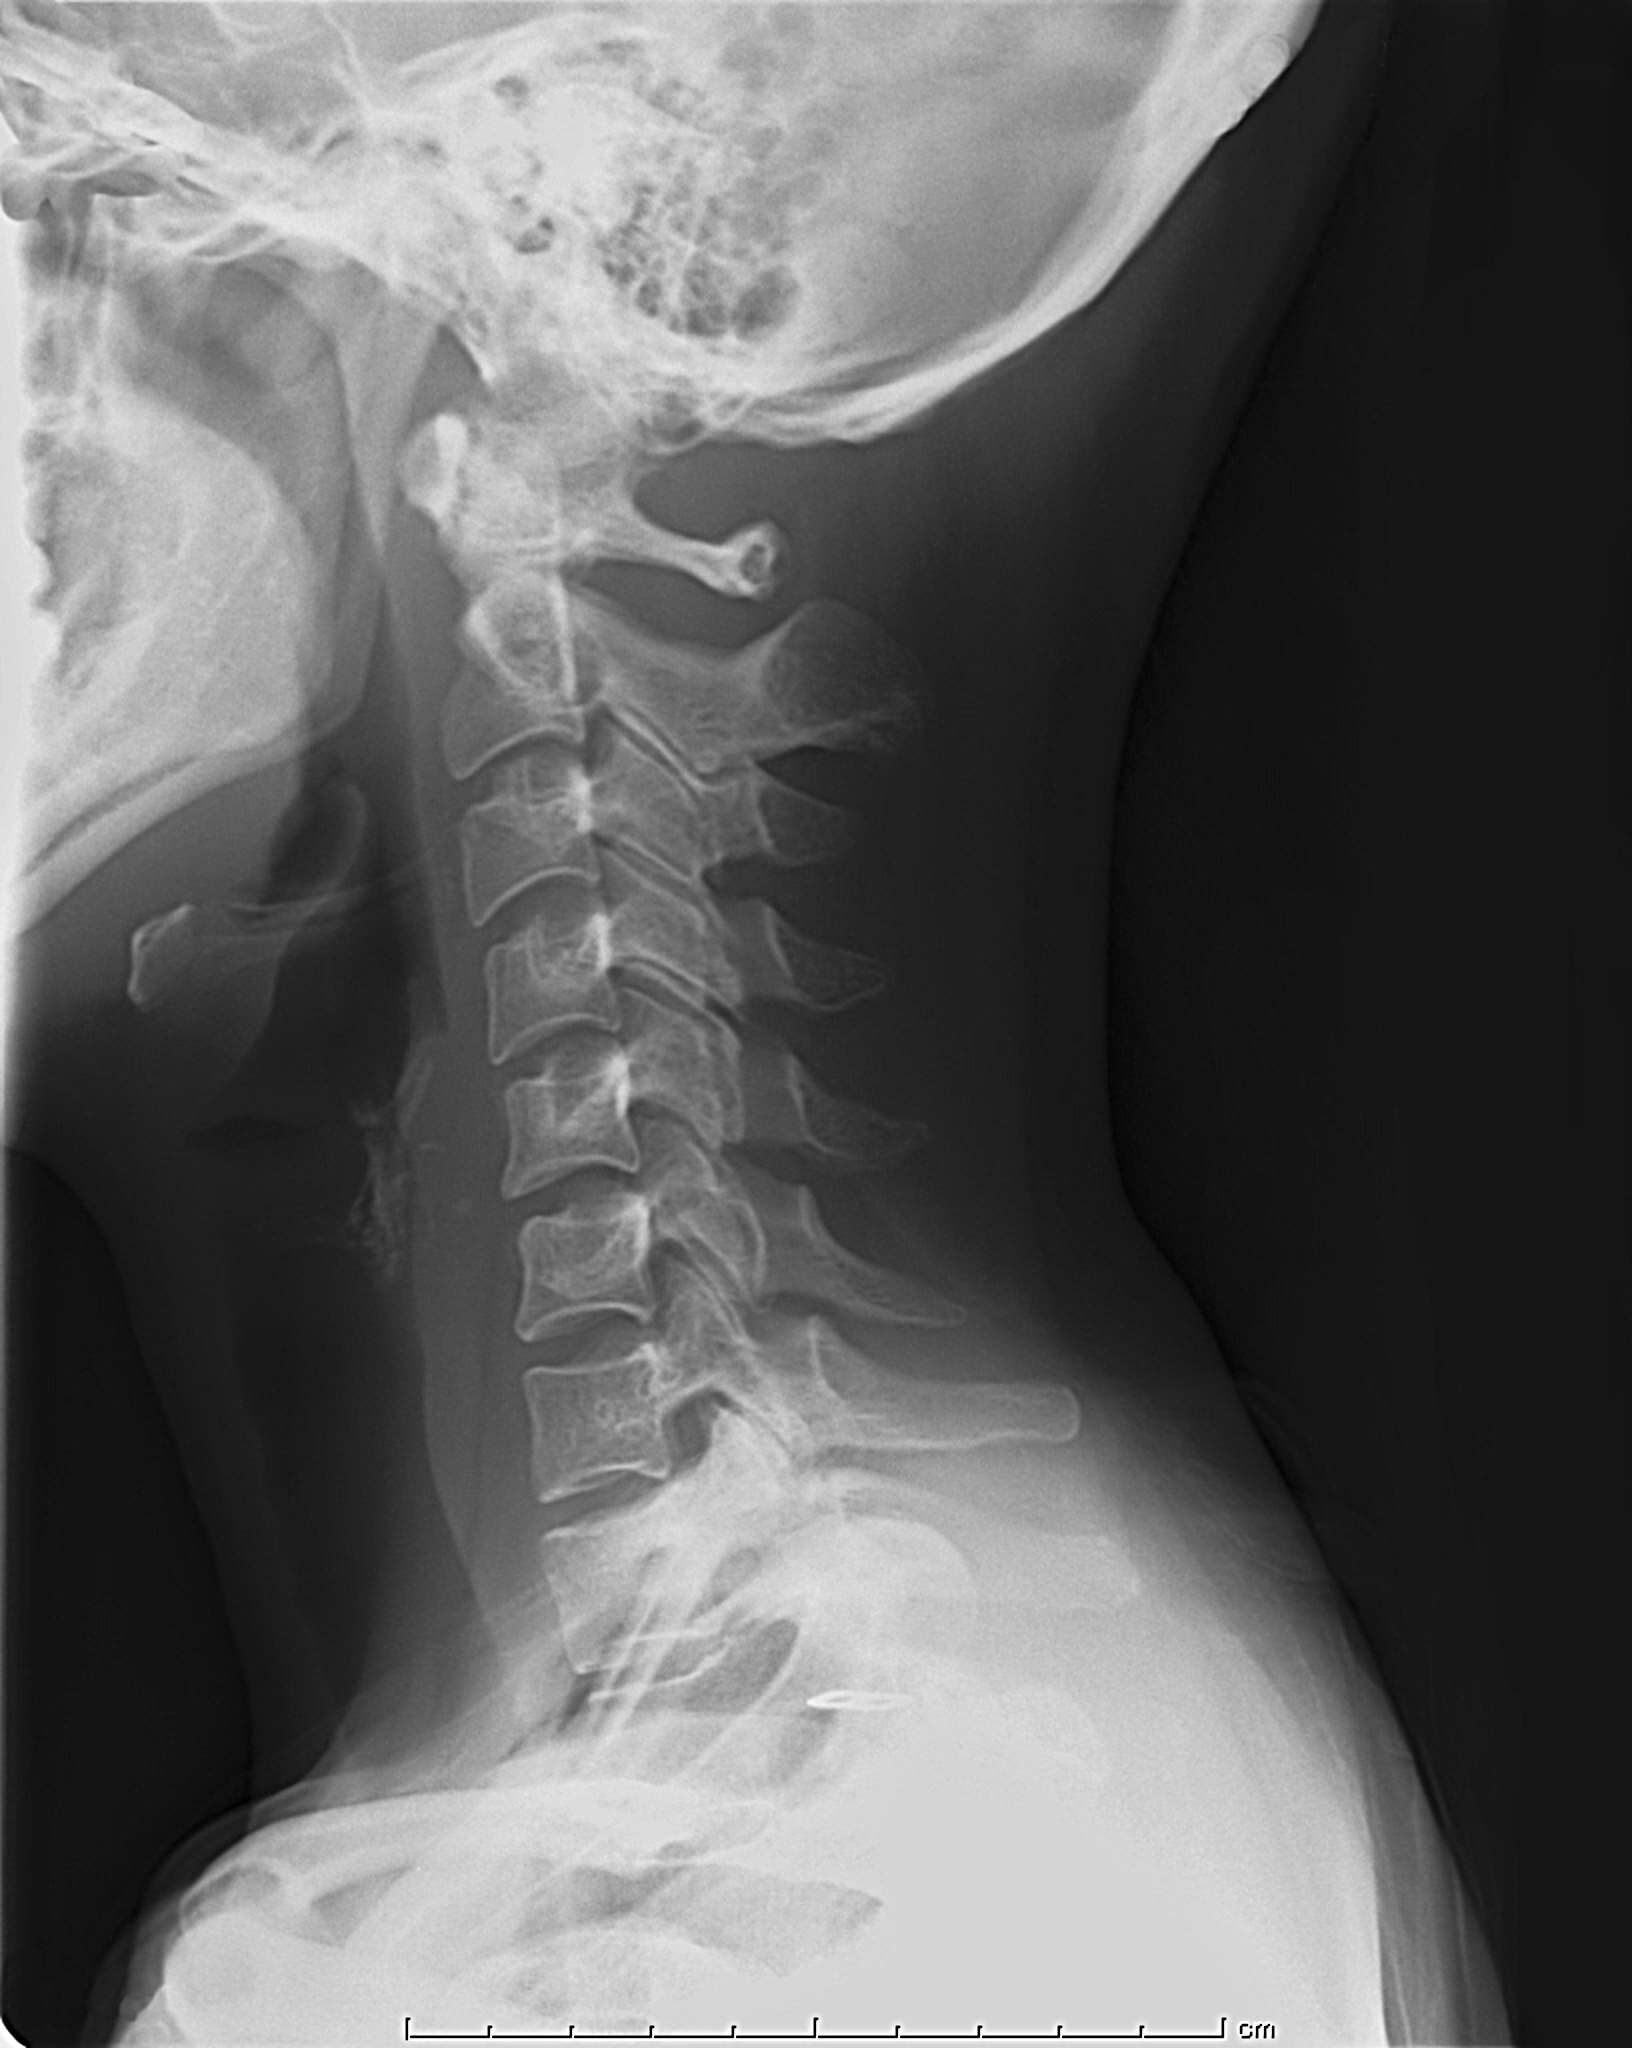

file3_title

ストレートネック(頚X線)